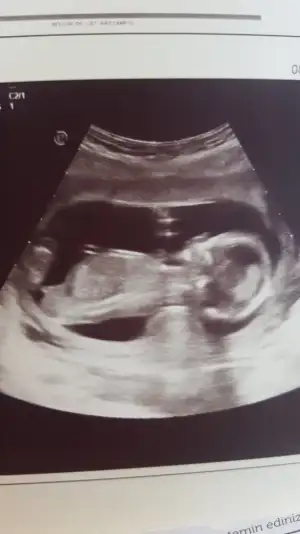

Arada kaldım ama kız gibi geldi bana Canım doktorun tahmin de bulundu muArkadaşlar yorum yapabilir misiniz 14 haftalık 2 boyutlu vermedi